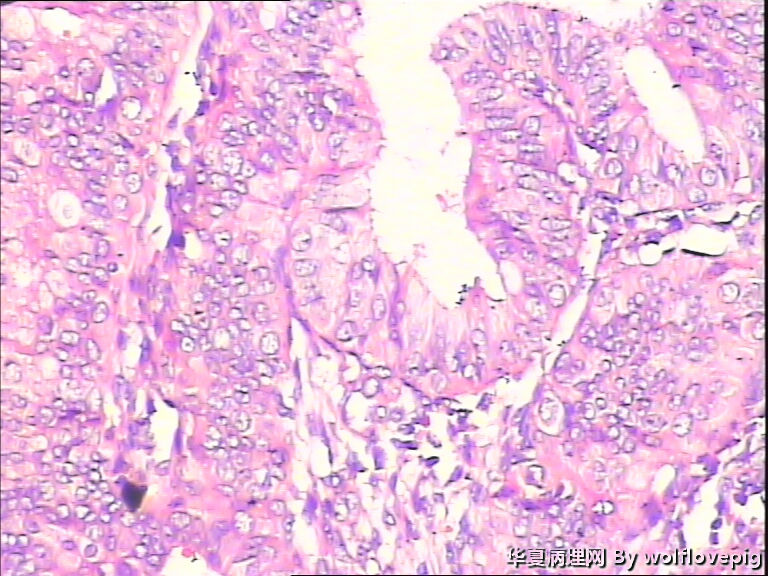

48y

子宫内膜复杂性非典型增生(有没有癌变,待制作优良的切片再诊断吧)。

复杂性非典型增生

简单型增生过长,48岁的女性,可能是转型的时候,而且内膜的共壁不是很明显,腺管的上皮增生层次也不是很明显,腺、间质比例较正常,所以有一点的异型不用太担心。同时刮宫既是诊断、又是治疗,可以妇科激素用药。

复杂型增生伴腺体增生活跃。

子宫内膜复杂性非典型增生

复杂性非典型增生(EIN)